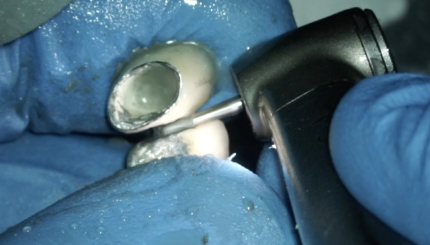

36 ИЗВЛЕЧЕНИЕ ВКЛАДКИ КХС

17 апреля 2025